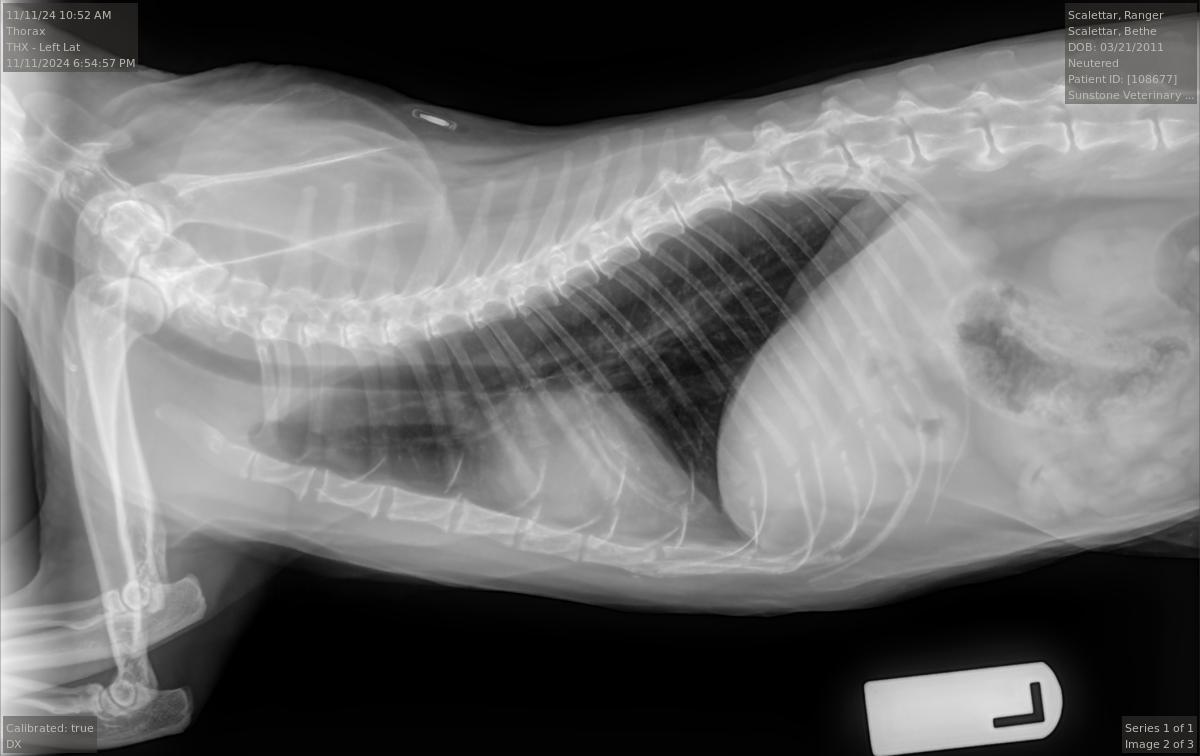

Veterinary diagnostic radiographic studies of the thorax and/or abdomen typically include at

least two projections: (1) a right (R) or left (L) lateral view, and (2) a ventrodorsal (VD) or

dorsoventral (DV) view. Right and left lateral views are taken with the animal lying on its right

(R) or left (L) side, respectively. Ventrodorsal and dorsoventral views are taken with the animal

lying on its back (VD) or stomach (DV), respectively. Radiopaque markers (e.g., “L” and “R”) are

placed near the animal to distinguish the views.

Projection radiographs lack depth information because the intensity of each point in the image

is a superposition of all structures along a given straight-line X-ray trajectory through the body.

However, by taking images along at least two orthogonal directions (e.g., R or L AND VD or DV),

the veterinarian can obtain three-dimensional information from the two-dimensional images.

For example, the pairs of superimposed ribs visible in the accompanying L and R radiographs

are visible as separate left and right ribs in the VD view. Taking both L and R views, or both VD

and DV views, can yield additional information.

The radiologist stated that the Ranger's radiographs were largely normal for an older cat. In

particular, they show arthritic changes in both elbows and the middle back. However, the

images did not show any abnormalities in the lungs and only mild, if any, enlargement of the

heart. Overall, these were good results.